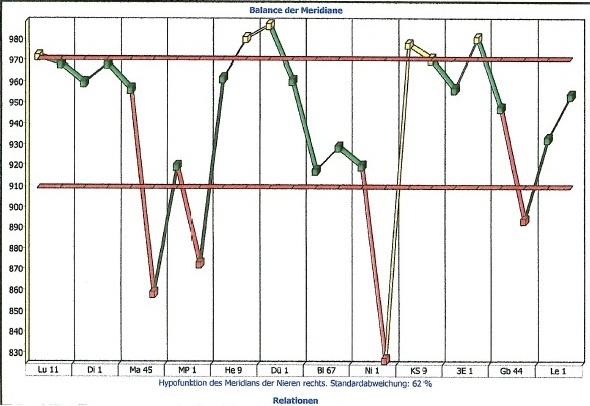

Nachfolgend Ergebnisse einer Studie, die über die Messung des menschlichen Meridiansystems aus der Traditionellen Chinesischen Medizin durchgeführt wurde, vor und nach der Betrachtung von Elementarkunst.

Sie können unter Fakten, Ergebnisse aus meiner Studie über die Wirkung der Initiativbilder einsehen, unter "Indirekt" Person 1 und 2 vorher und nachher.